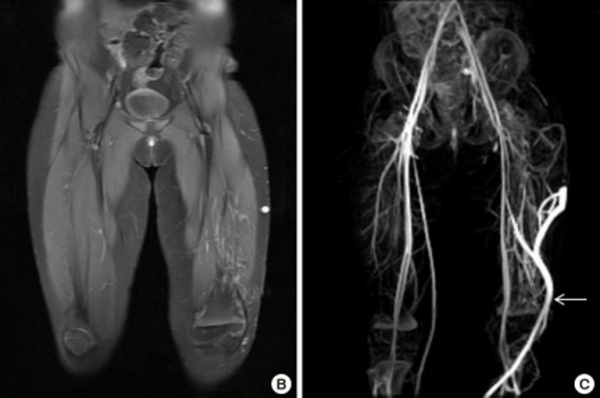

МРТ нижней конечности. Расширенная поверхностная венозная сеть и гипертрофия мягких тканей. Белая стрелка - эмбриональная боковая краевая вена.